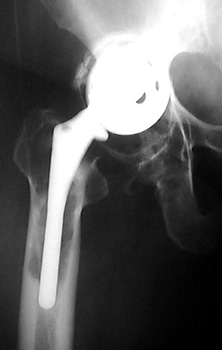

INFECTION Progressive interface widening about acetabular component